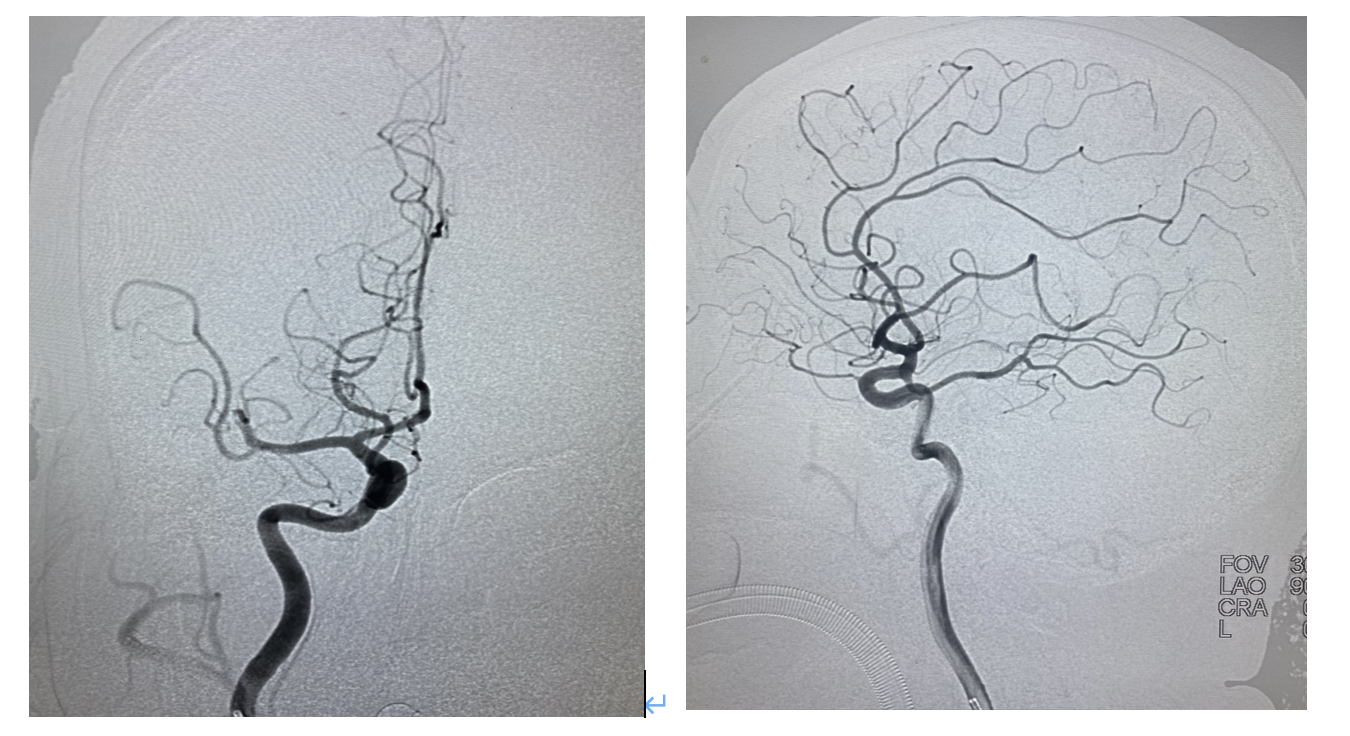

1、术中造影可见右侧大脑中动脉M2段上干闭塞,同侧大脑前无明显代偿,故不考虑狭窄,判断为血栓形成,尝试抽拉结合开通血管。

2、心玮吞川抽吸导管到达海绵窦段,微导管在微导丝的引导下无阻力进入较为平滑的M2远端,冒烟证实在血管真腔。

3、心玮4-20取栓支架到位释放,等待5分钟,在支架铆钉及微导管的支撑下,逐步跟进抽吸导管至M2闭塞处,撤出微导管,关闭滴注,利用SWIM技术,整体将取栓系统撤出体外,复查造影血流2b级,正位看局部似乎还有血栓,侧位及斜位看,似乎还有1支未通,给予动脉内替罗非班10ml/10分钟。

4、给予替罗非班后为进一步了解病变,行3D造影,最终证实M2分叉部一共有4支,开通3支,还有1支闭塞,指向额叶供血。

5、工作位路图,在中间导管高到位辅助下微导管超选M2闭塞分支,冒烟证实血管真腔,释放心玮4-20取栓支架。

6、关闭滴注,中间导管到达M2分叉部,缓慢轻拉支架入中间导管整体撤出体外,可见支架远端附着血栓。 术后即刻造影,闭塞分支血管再通,M2闭塞处的可疑血栓消失,至此4支血管全部通畅,血流3级,结束手术。